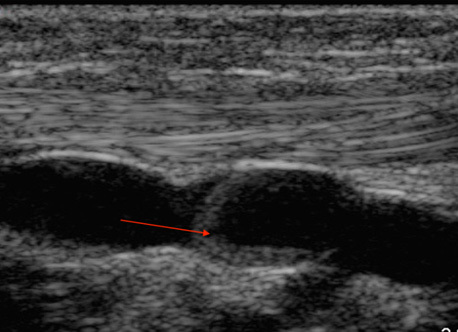

Peripheral IV (PIV) Thrombus at Valve Site Image